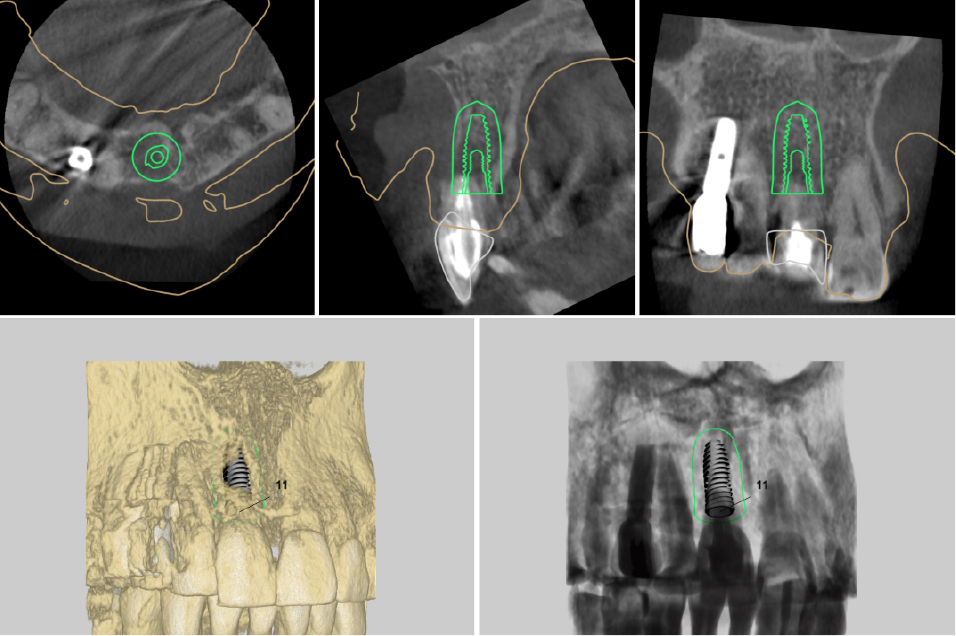

サージカルガイドとは、インプラントを埋め込むためのオーダーメイドの「手術用テンプレート」です。事前に撮影したCTデータを用いてコンピューター上で緻密なシミュレーションを行い、インプラントを埋入する最適な位置、深さ、角度を正確に設定して作製します。

コンピュータ上で、骨の量や形、神経・血管の位置を正確に把握し、インプラントがどのように入るかをシミュレーションします。

- 精密検査: 3DでのCT撮影を行い、顎の骨や神経、血管の位置などを詳細に確認します。

- シミュレーション: 取得したデータを基に、コンピューター上でインプラントの最適な埋入位置をシミュレーションします。

- ガイド作製: シミュレーション結果に基づいて、正確な位置にインプラントを埋入するためのサージカルガイドを作製します。